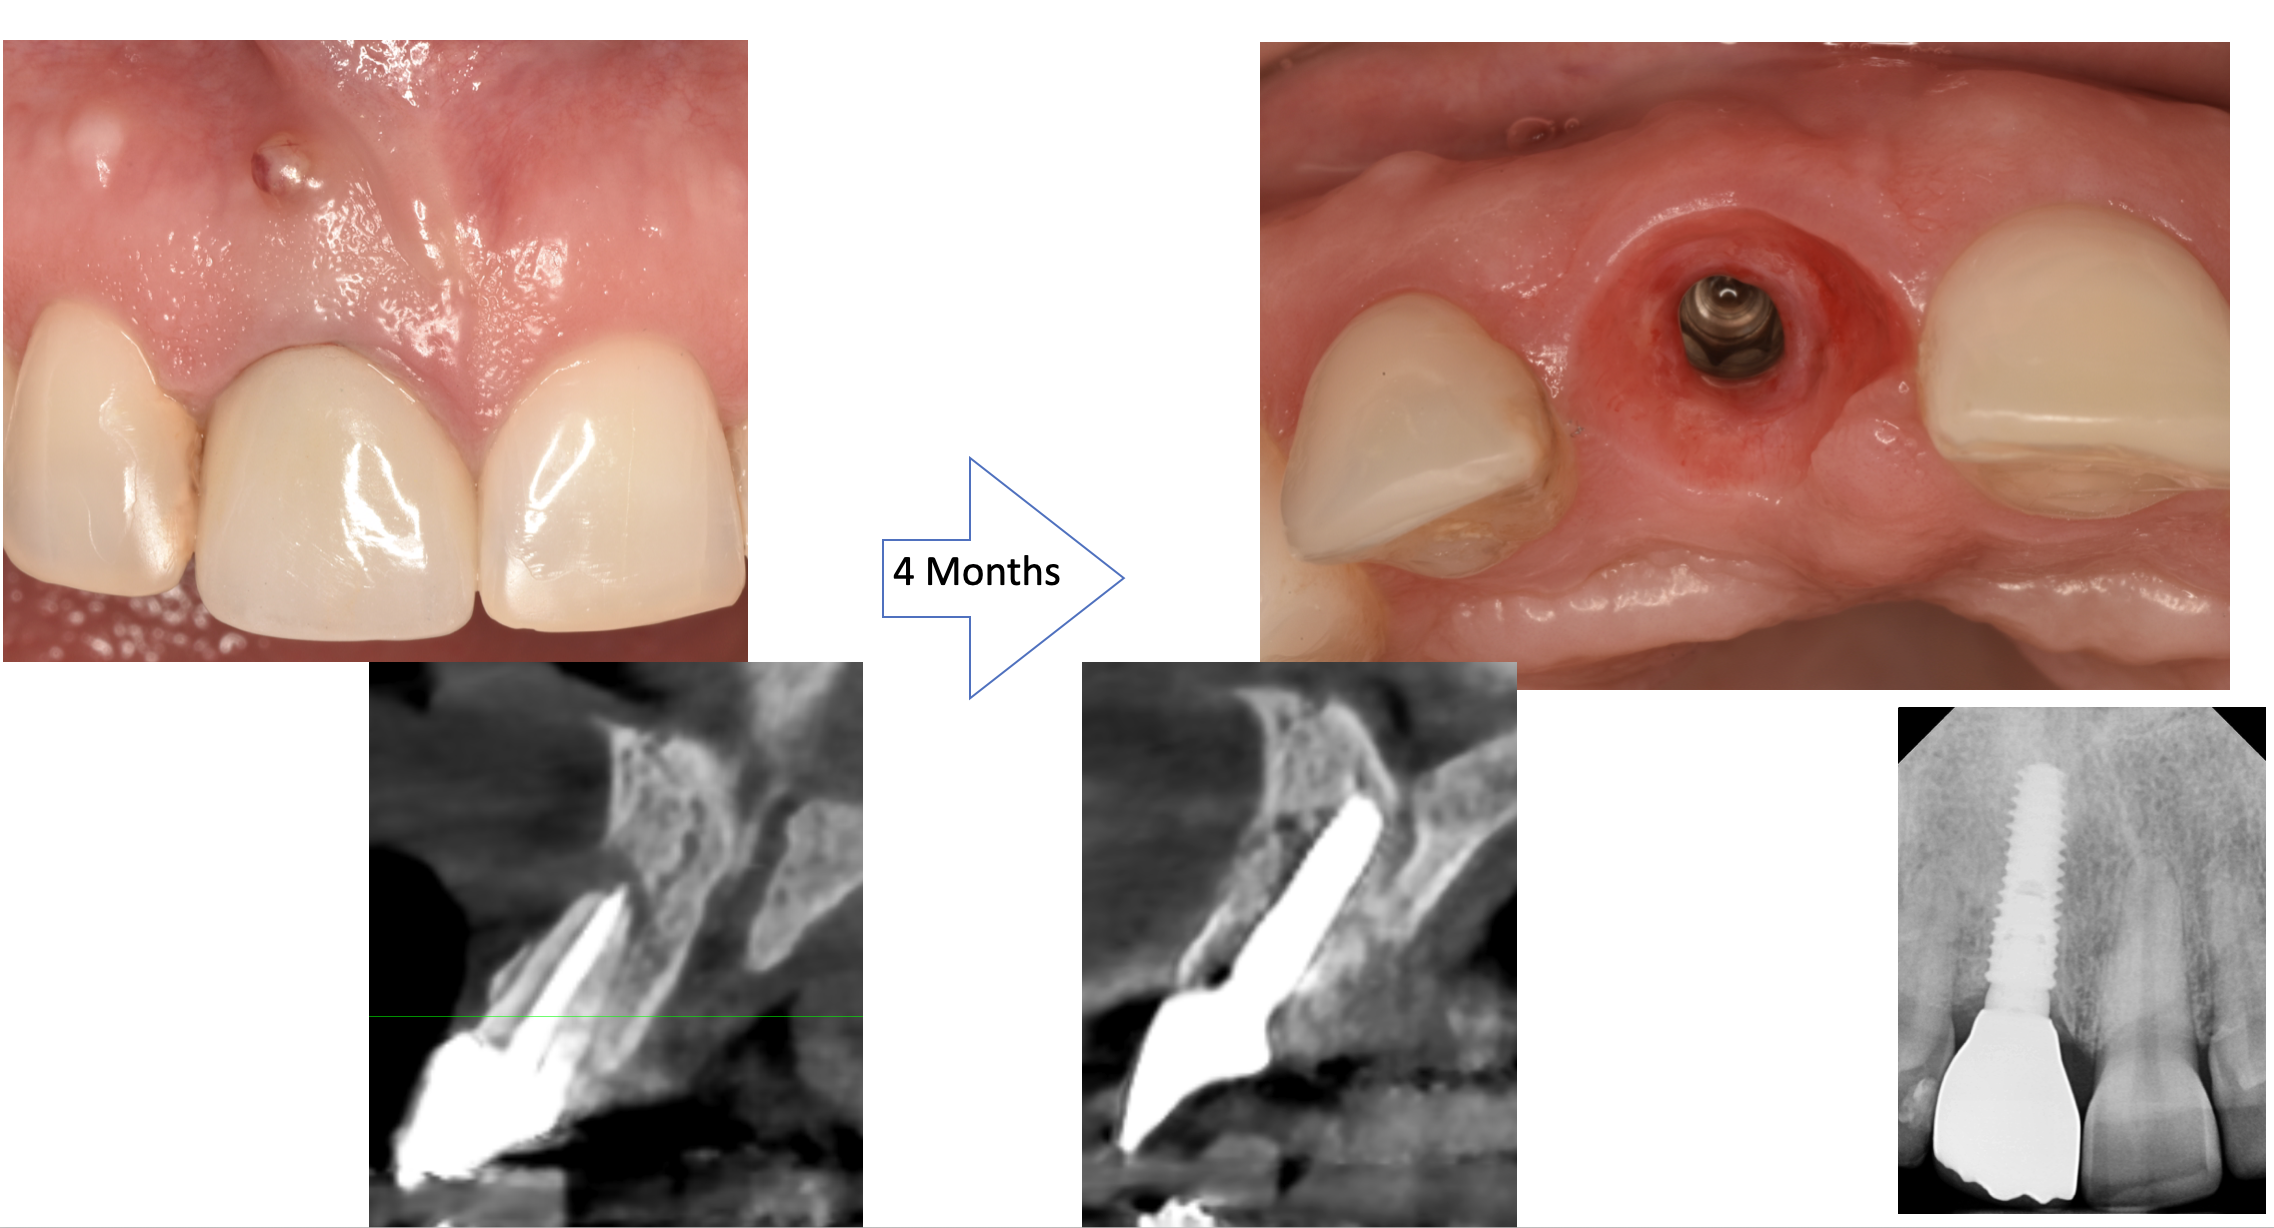

Each case is documented with clinical pictures before, after and during operation. For most of the cases there is surgical video. CBCT before, in the OP day and 4 months after, or longer period of time will demonstrate the volume of buccal bone and soft tissue. Depends of time available, between 13 and 20 clinical cases can be shown.